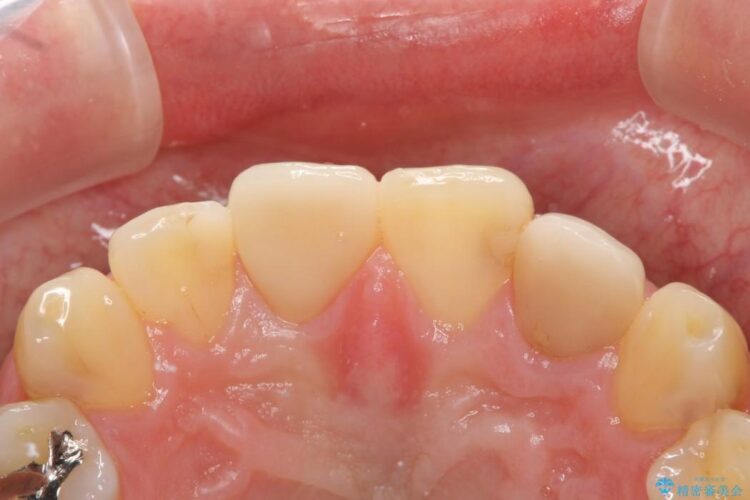

神経に届く一歩手前の虫歯を前歯に認めました。

虫歯の範囲が大きいため詰め物ではなく、被せ物を使用した治療を行うこととしました。

今回のケースでは丁寧に虫歯を取りきることにより、神経を保存することができました。